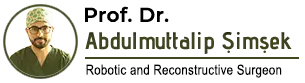

Ventral buccal mucosal urethroplasty

Notice: Trying to access array offset on value of type null in /home/u9176434/en.uretradarligi.com/wp-content/plugins/js_composer/include/autoload/vc-shortcode-autoloader.php on line 64 Notice: Trying to access array offset on value of type null in /home/u9176434/en.uretradarligi.com/wp-content/plugins/js_composer/include/autoload/vc-shortcode-autoloader.php on line 64 Notice: Trying to access array offset on value of type null in /home/u9176434/en.uretradarligi.com/wp-content/plugins/js_composer/include/autoload/vc-shortcode-autoloader.php on line 64 Ventral buccal mucosal urethroplasty ÖZGEÇMİŞ Yaş: 64…